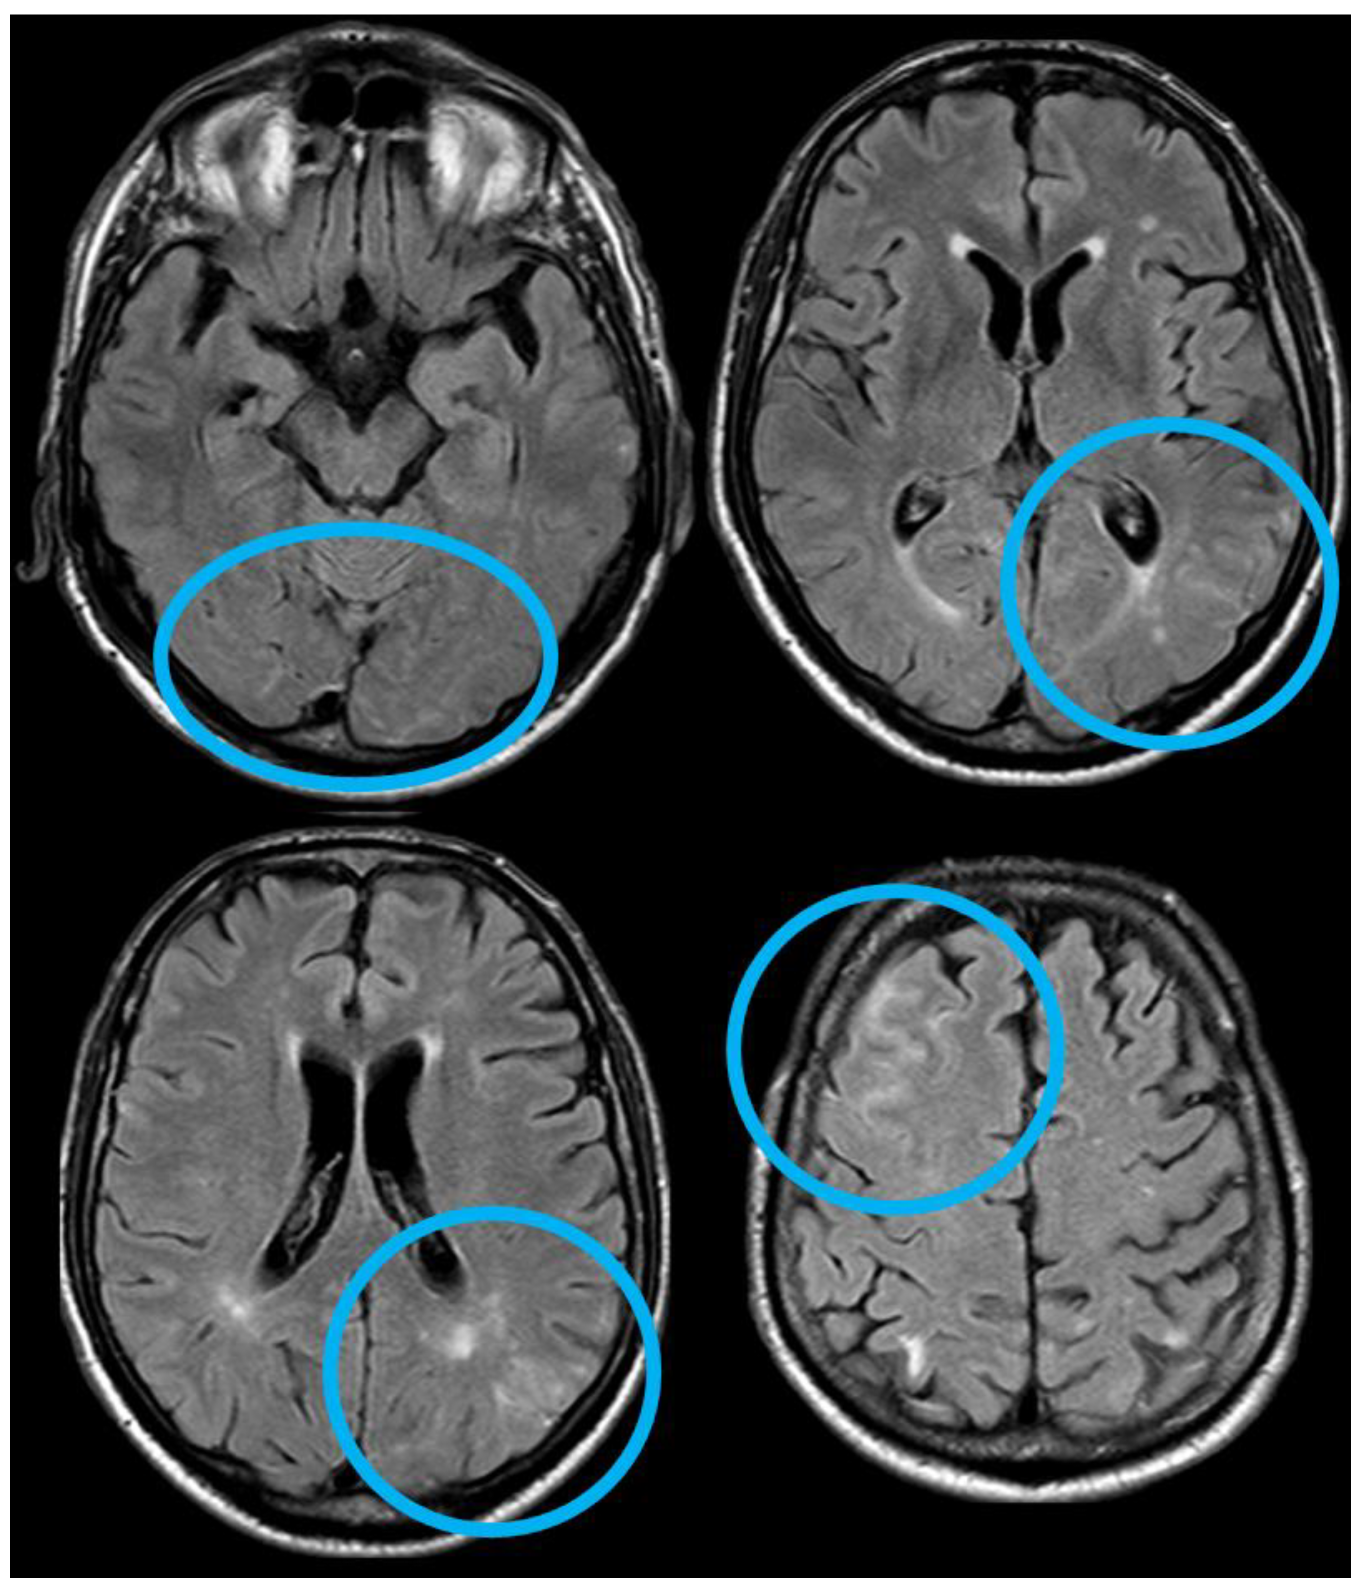

4. December 2015: Ischemic Stroke